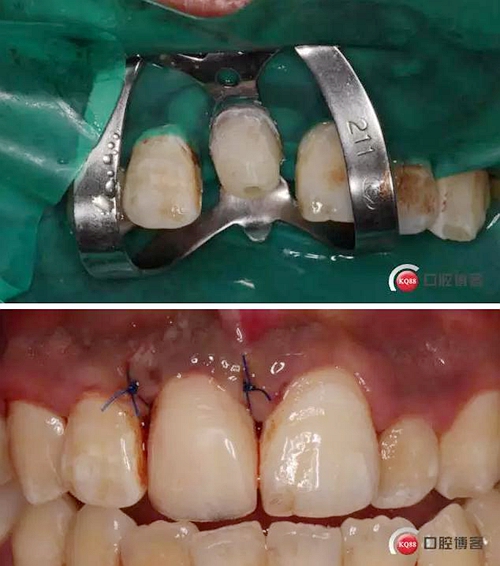

初診檢查:A1殘冠,斷面平齊牙齦,根內(nèi)有繼發(fā)齲。牙齦略紅腫,齦緣高度過(guò)低。跟患者溝通方案,患者希望盡量保存患牙

溝通后局麻下切齦,翻瓣,去骨,做冠延長(zhǎng)。翻瓣后上橡皮障 去盡繼發(fā)齲,打樁堆核,暫冠修復(fù)引導(dǎo)牙齦成型。